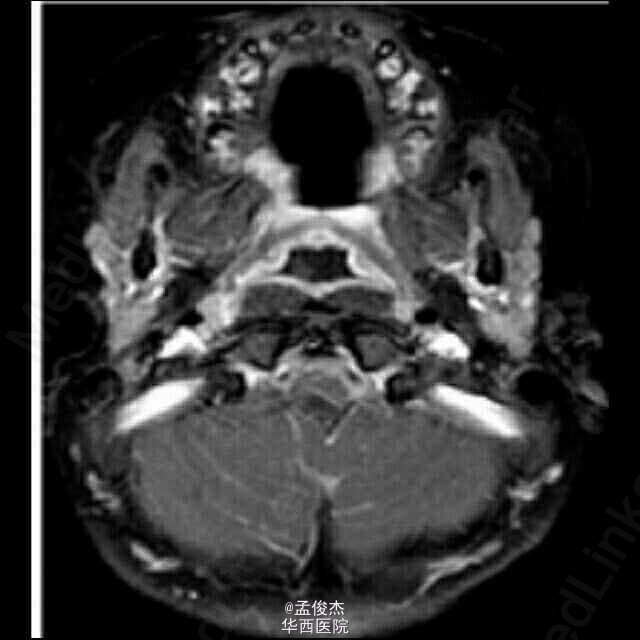

患儿女,33个月大,发热3天,体温最高102°F,伴有心动过速,130次/分。阵发性癫痫一天,伴有尖叫,双手紧握,双眼上翻,症状持续几秒到一分钟,仅在睡眠中发生。患儿在睡眠中易醒,既往有轻度哮喘。查体,黏膜干燥,余者无明显异常,血常规电解质水平检查无异常,血气分析示碳酸氢盐12 mmol/L,血糖69 mg/dL,尿中有大量酮体;脑脊液检查显示每立方毫米2个白细胞,1040个红细胞。头颅CT无明显异常,腹部超声无明显异常。 予总量为40 mL/kg 的生理盐水治疗心动过速,患儿心率恢复正常。使用万古霉素,头孢曲松钠治疗可能存在的败血症。 住院期间患者的癫痫持续发作,逐渐发展为吞咽困难,无法说话和右侧肢体无力。血尿脑脊液培养结果为阴性,停止输入抗生素。脑电图无异常。MRI示小脑右半球T2信号增高提示小脑水肿。碳酸氢盐升高至18 mmol/L,尿液中持续存在大量酮体。酮硫解酶 基因检测正常。CT检查示回肠末端的不规则增厚,管状软组织突出入盲肠。病毒PCR示患儿H1N1感染。 最终诊断为病毒性脑炎。患儿接受奥司他韦治疗后,明显好转,若干月后出院。 病毒相关脑炎与甲型流感关系最为密切,常见于5岁儿童。感染一周后出现症状,死亡率为37%。流感病毒导致的脑损伤并不经常表现为脑炎而是表现为代谢障碍,酮体增加,小脑水肿。